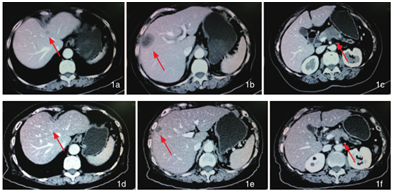

上图为治疗前CT,下图为治疗后CT

2013年9月初,经过两个疗程的海扶刀+基因全身热疗,经CT检查发现:胰腺肿瘤大部分消失,肝转移病灶消失、肺转移病灶、腹腔淋巴结转移灶基本消失,患者达到临床治愈的效果。目前已过2年,李女士仍然存活,在家中操持家务,享受天伦,在健康状态下生活。